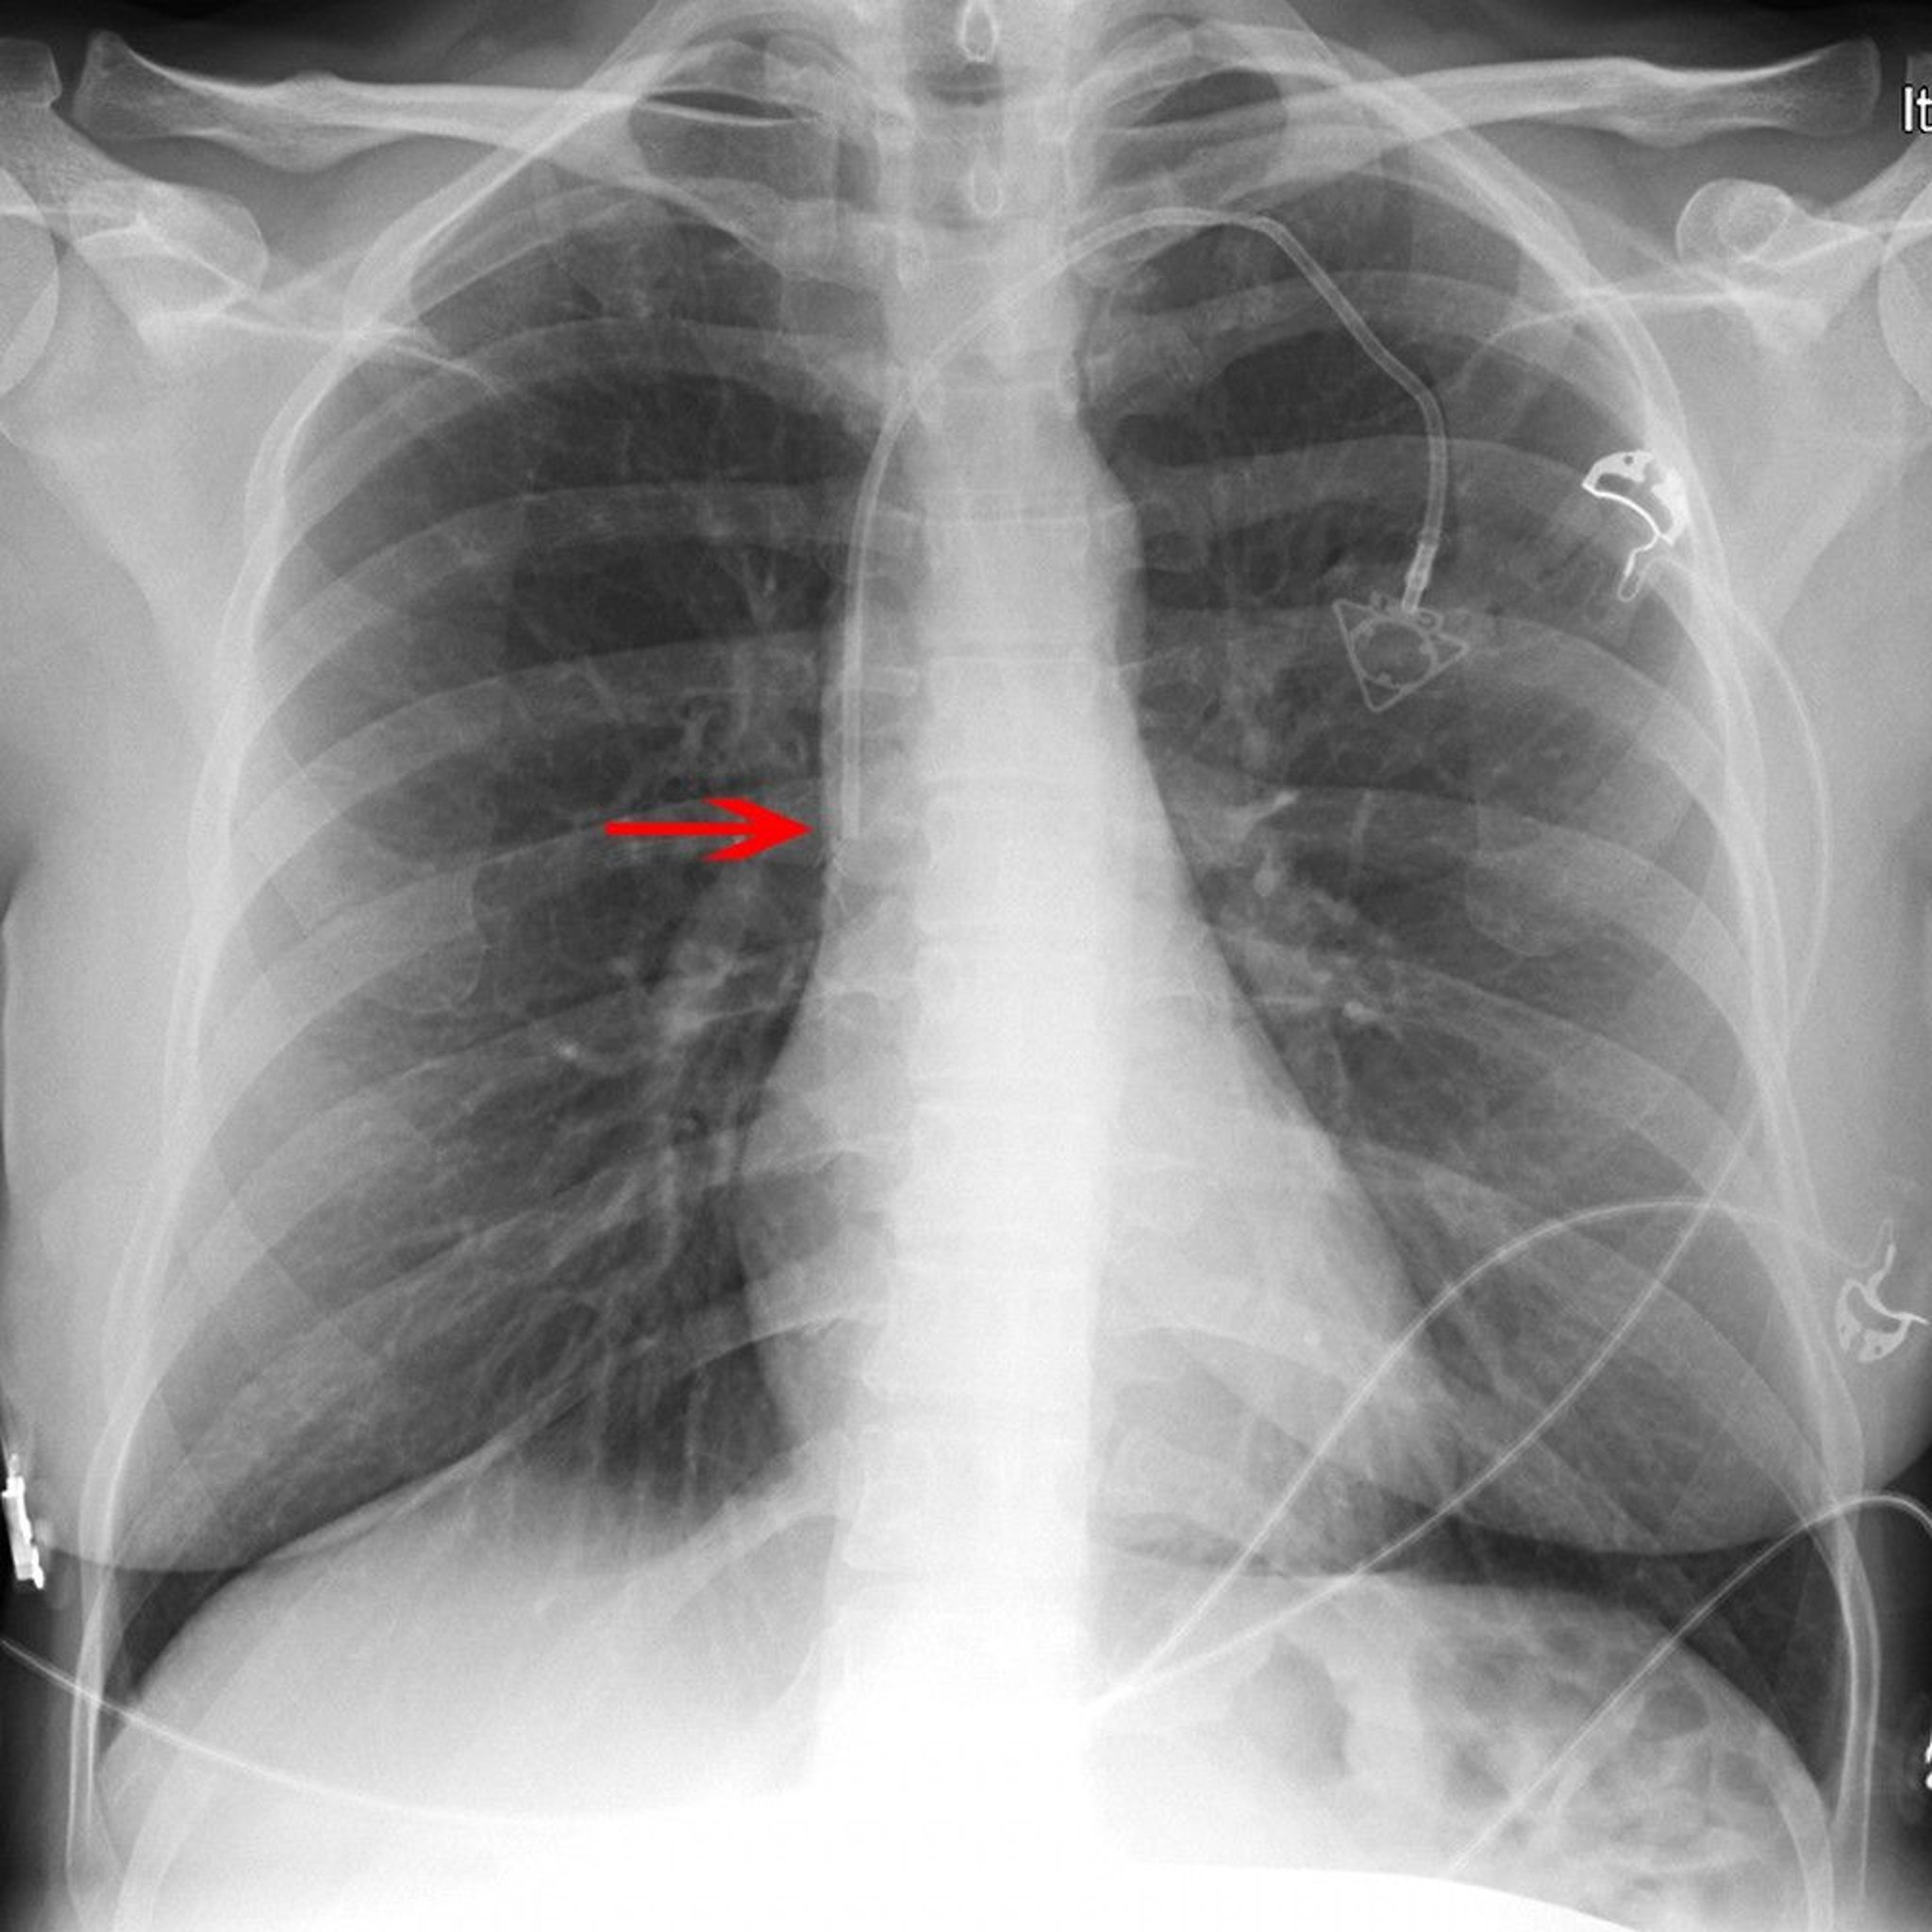

Radiograph of a Central Venous Catheter

The red arrow points to the tip of a left subclavian venous port catheter (placed appropriately in the lower superior vena cava).

© 2017 Elliot K. Fishman, MD.